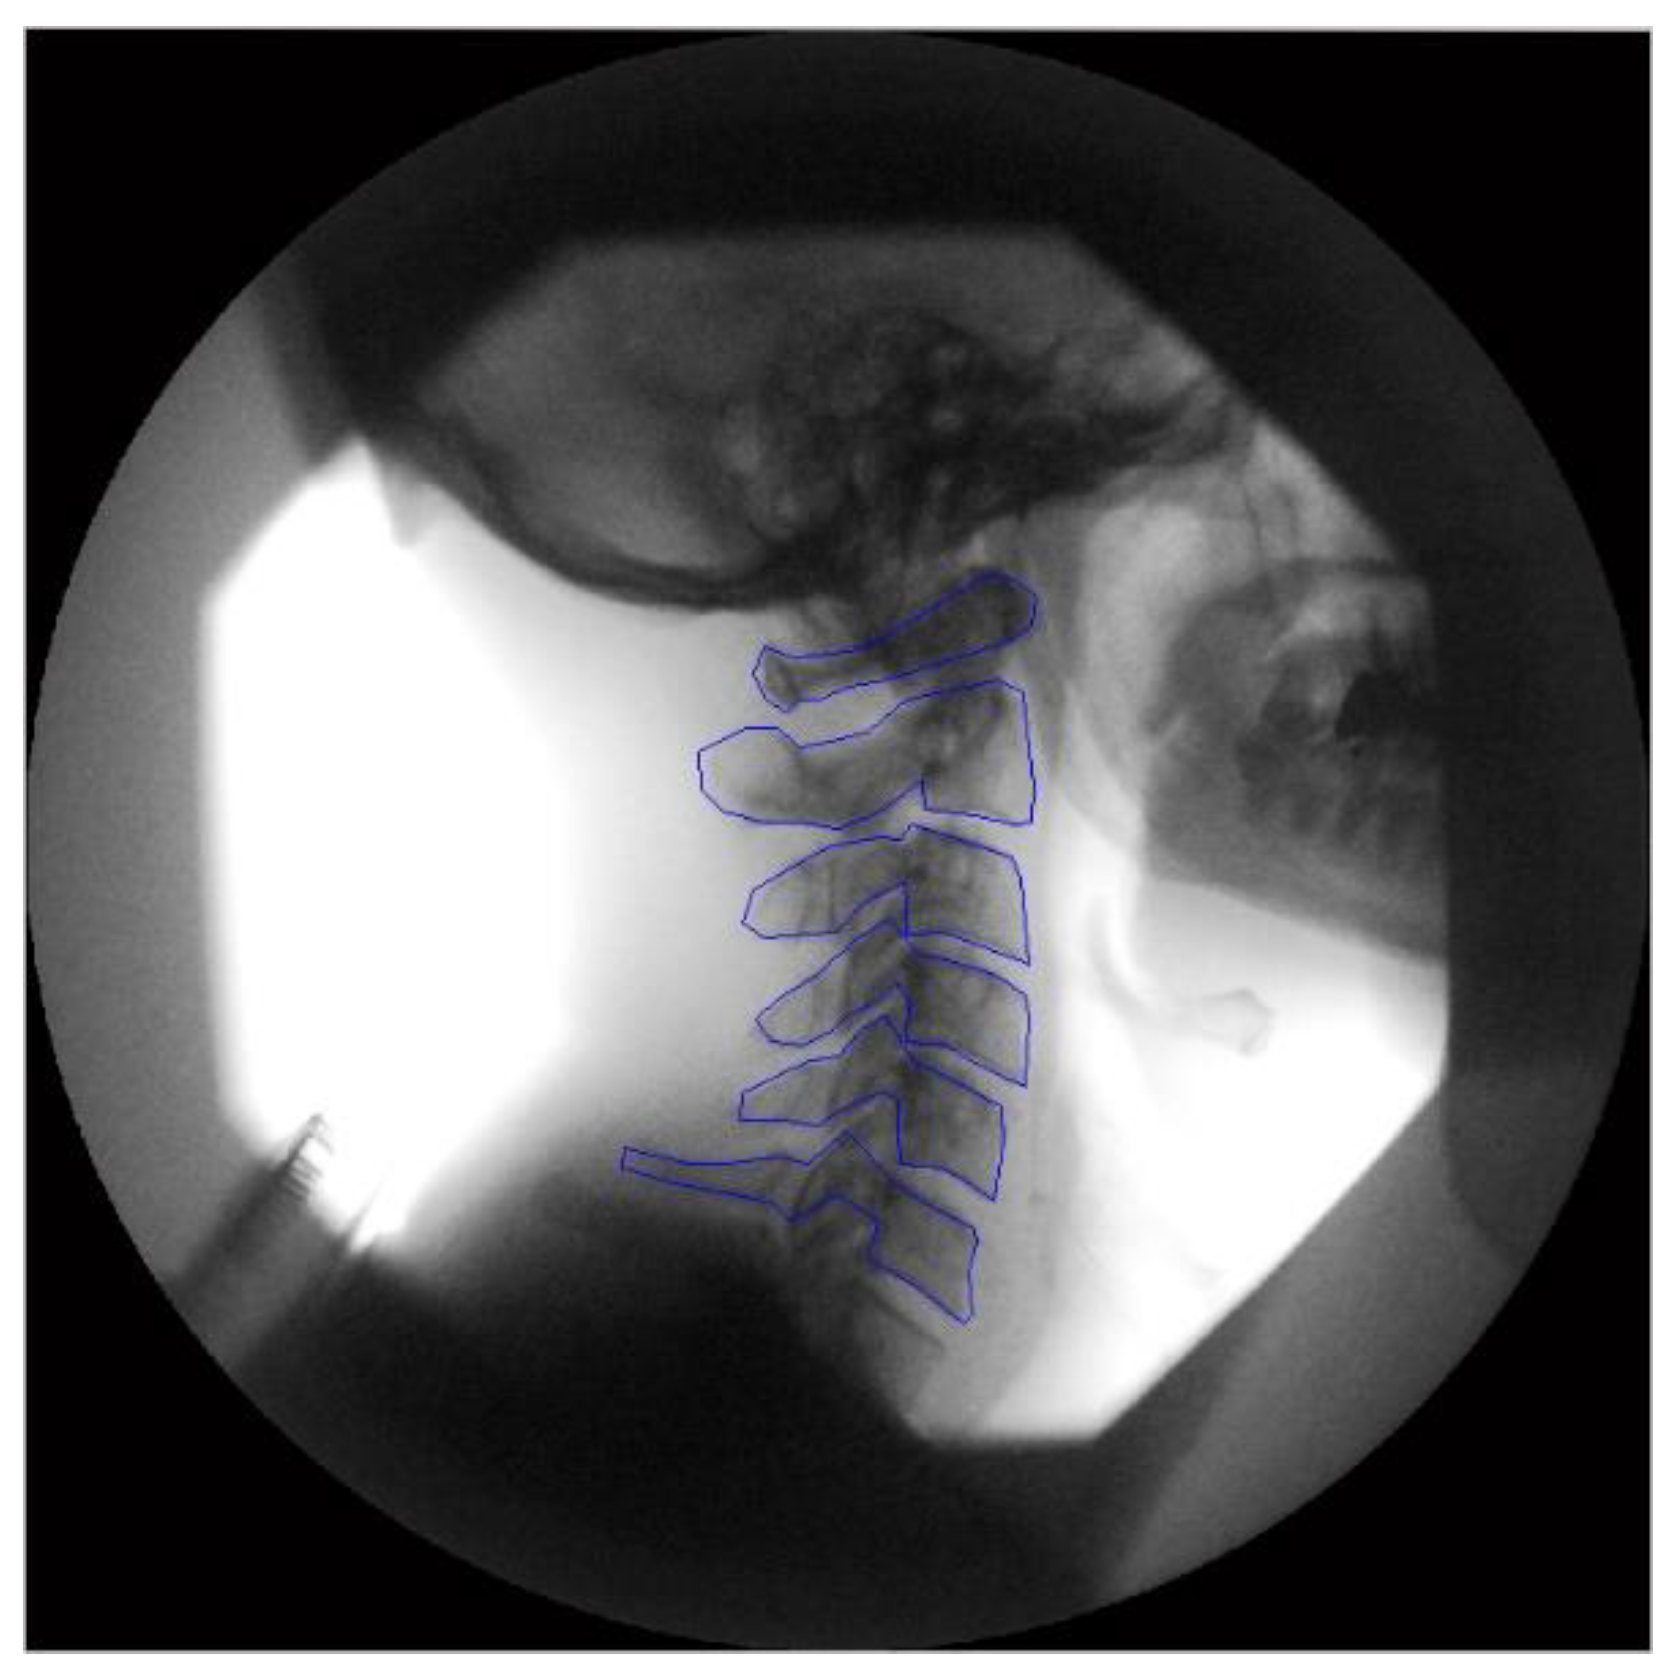

2.2. Image Acquisition

2.3. Image Analysis